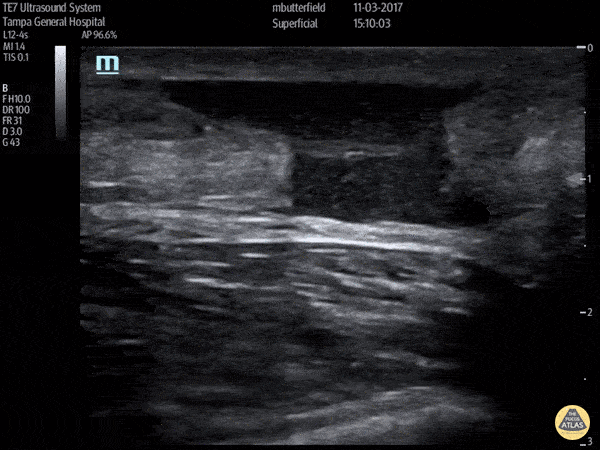

Musculoskeletal - Achilles Rupture (Long Axis)

Full thickness tear of right achilles tendon after a skateboarding accident. (Long Axis) Dr. Mike Butterfield